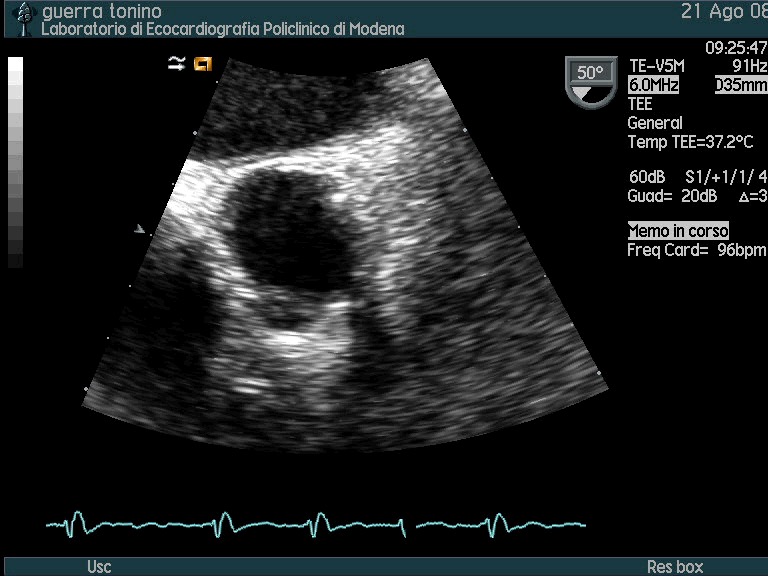

Ostruzione di protesi mitralica bidisco da panno e trombosi

Autore:

Mauro Pepi